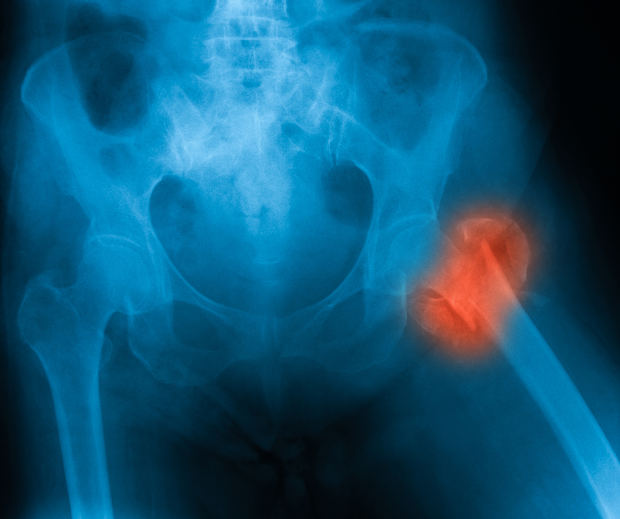

Osteopenia vs. osteoporosis: Understanding the difference

We often hear doctors using the term osteopenia and osteoporosis when referring to human bones, but there is a difference between the two. Understanding the difference can protect you and keep you mobile. When we look at the words osteopenia and osteoporosis, it’s easy to see how the two can be confused. Aside from the ...click here to read more